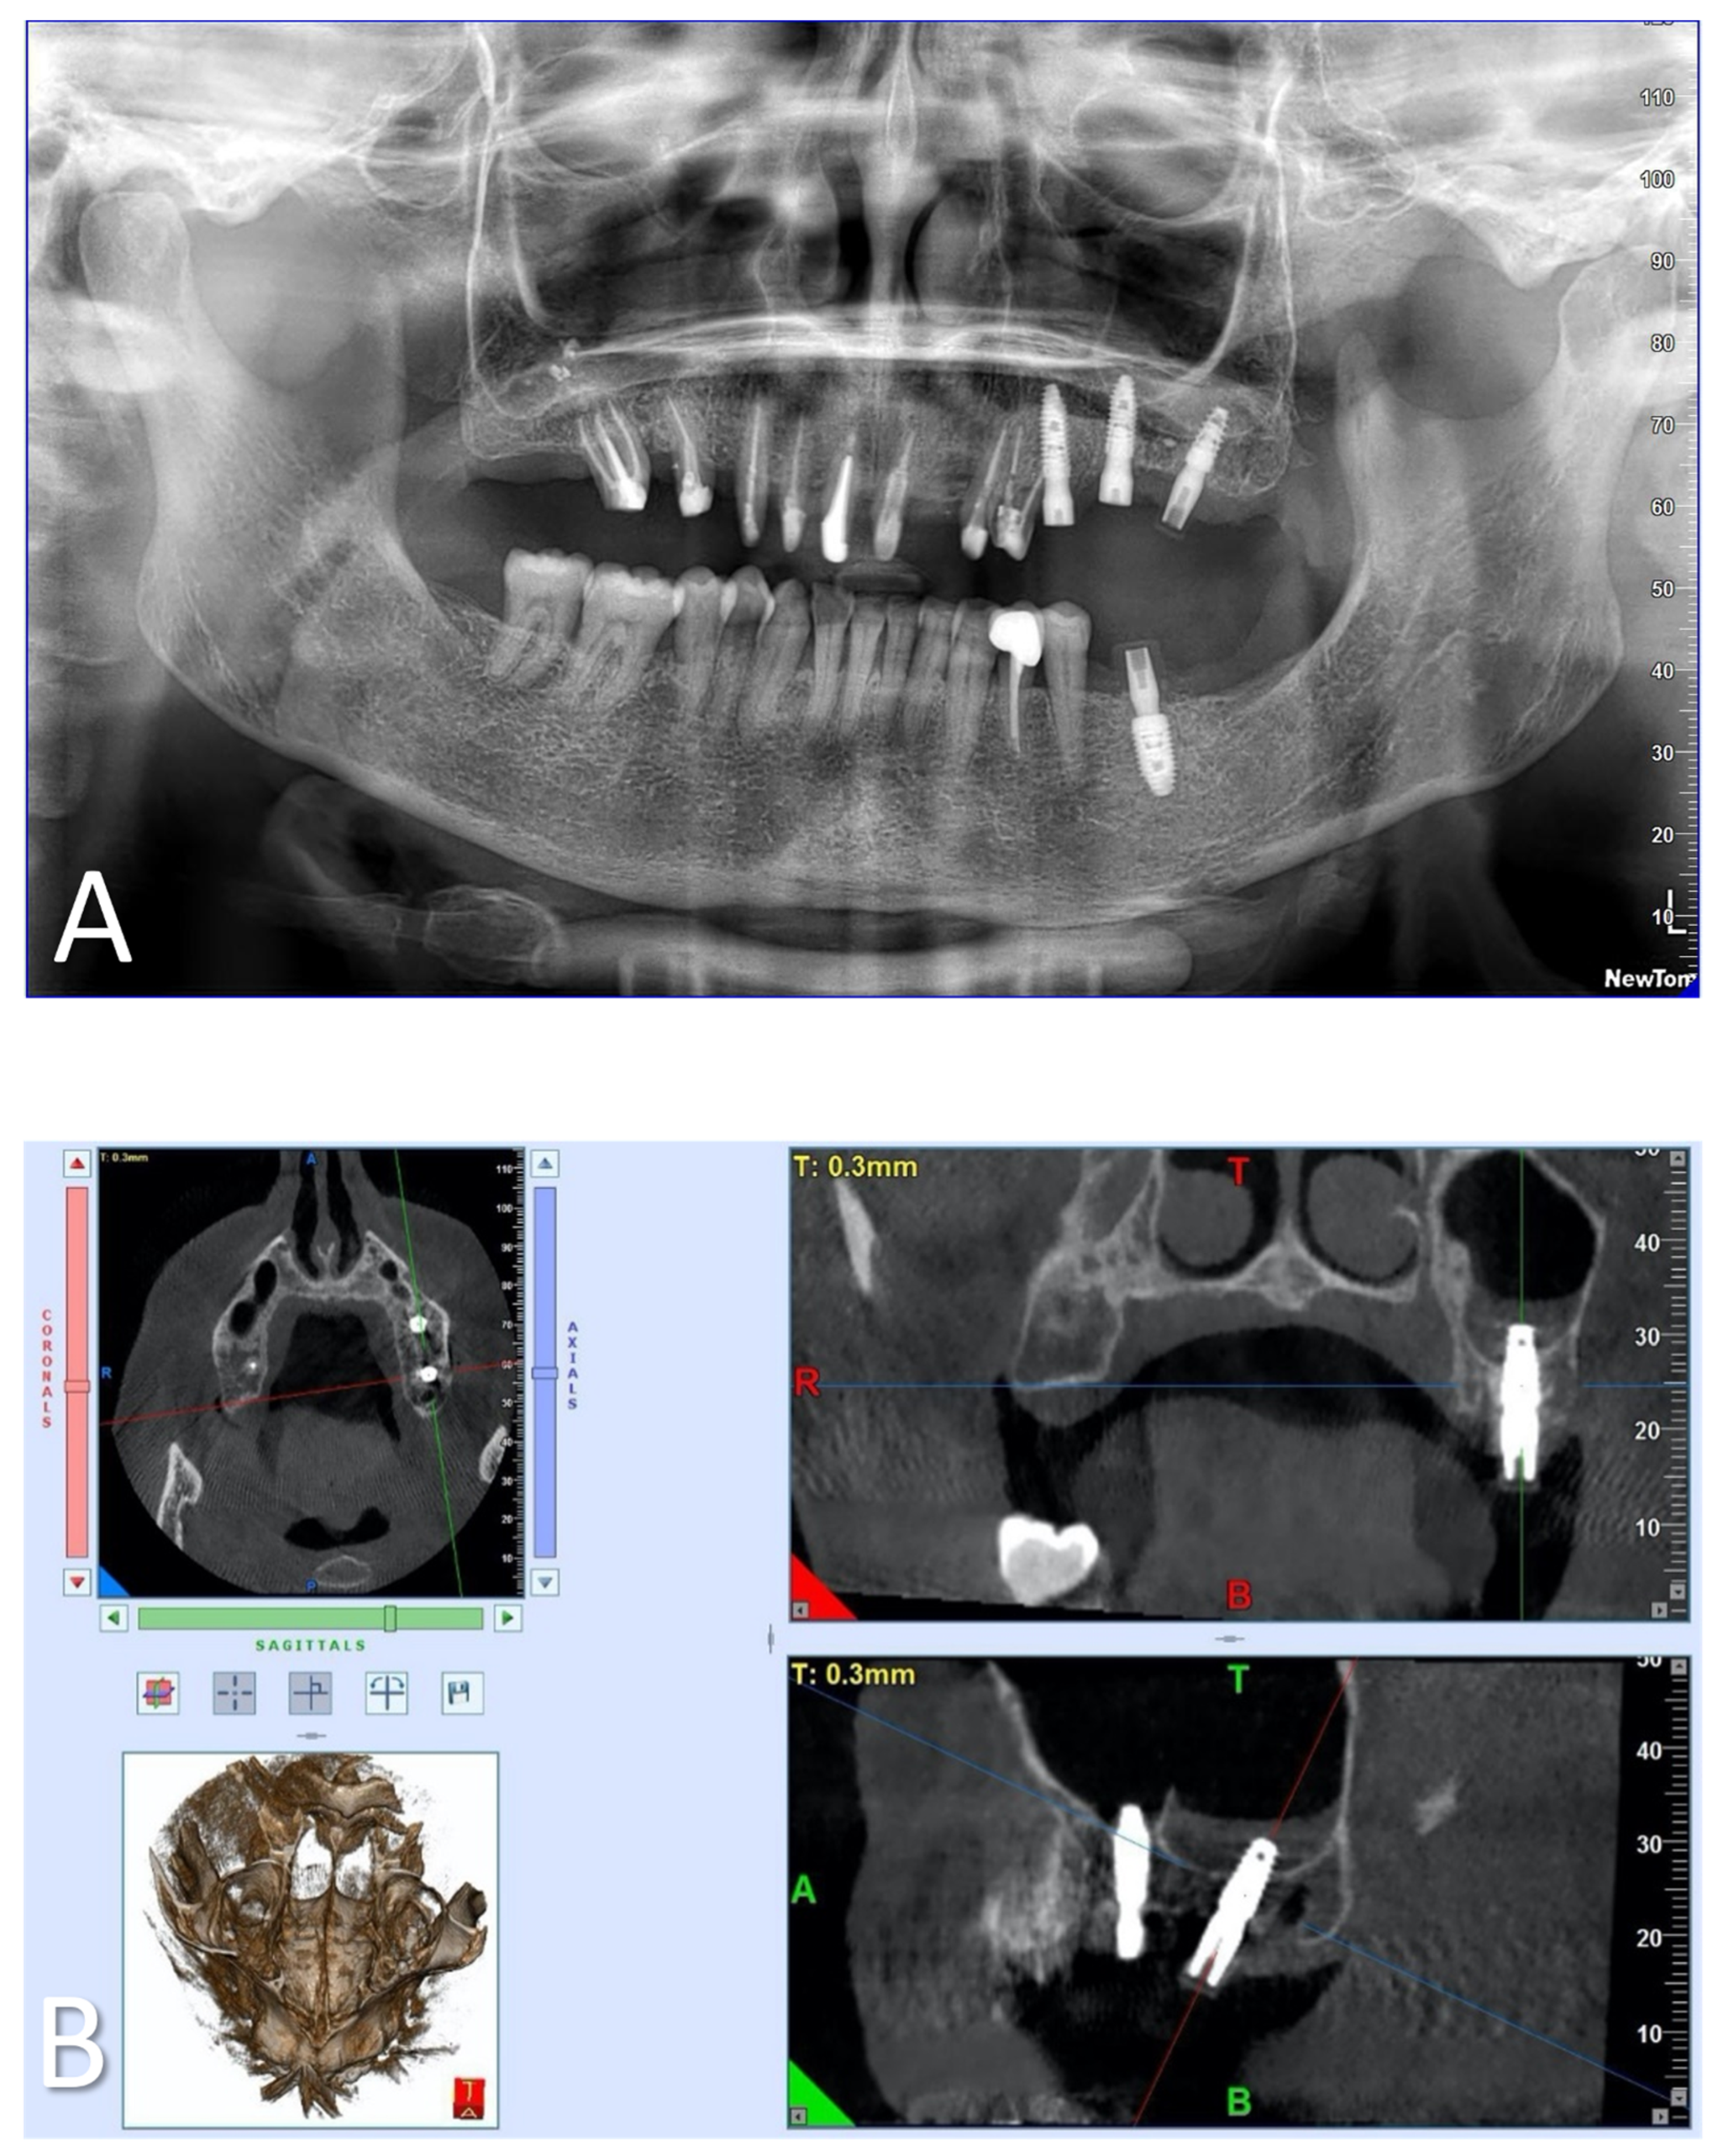

Case Report of a Dental Implant with Conometric Abutment–Prosthetic Cap Connection: Advanced High-Resolution Imaging and Peri-Implant Connective Tissue Performance

2. Materials and Methods

2.1. Samples